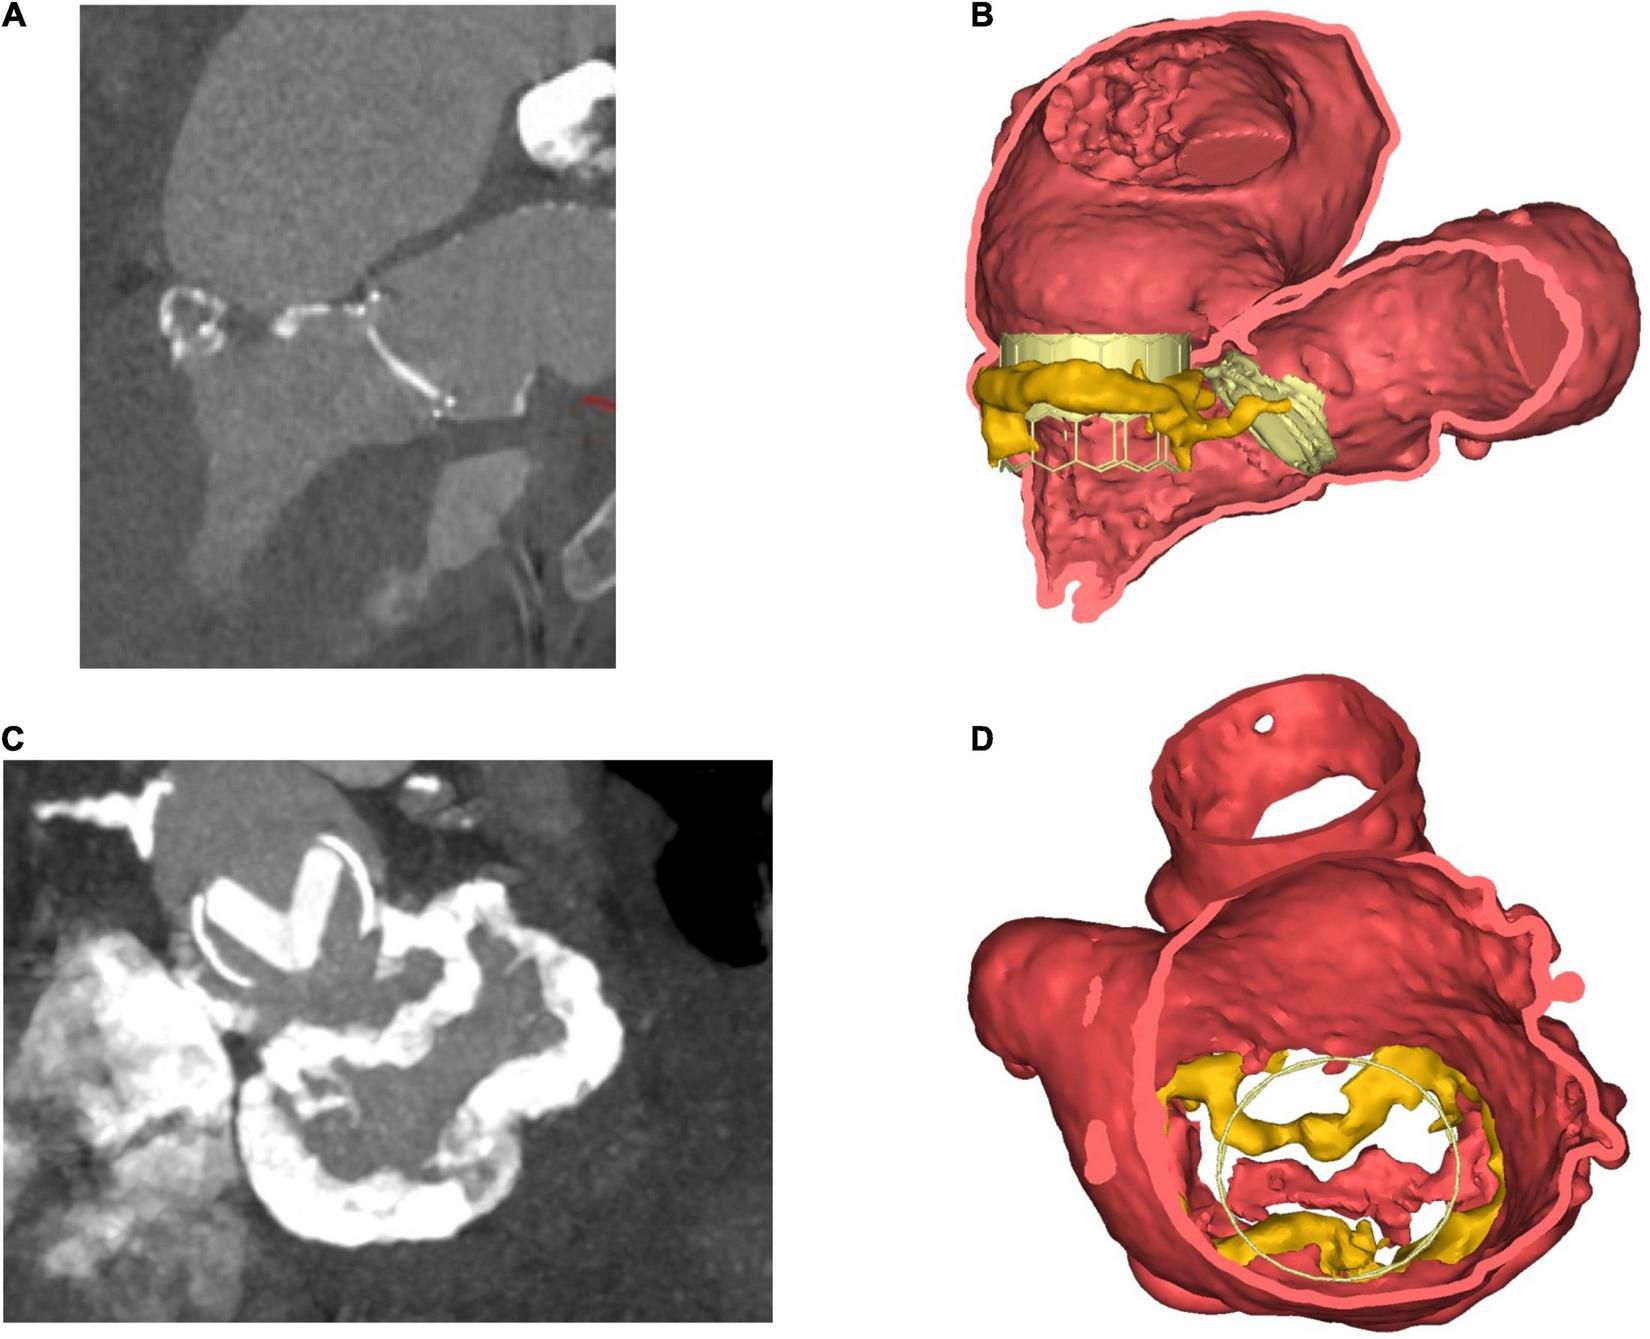

Mitral annular calcification itself can serve as a bed on which the new valve can anchor. In procedures involving the implantation of a TAVR prosthesis in the mitral valve position, non-circumferential or thin MAC can result in poor device sealing (67). MAC can also make it difficult to determine the correct position for valve deployment, with 17% of valve-in-MAC cases requiring a second valve deployed in an early study. The population in this study was at high surgical risk (STS score 14.4 ± 9.5%) and had a 30-day all-cause mortality of 30% (68). In order to plan a TMVR, 3D reconstructions can be created and valve implantation simulated using dedicated off-line software (Figure 3).

FIGURE 3

Steps in planning for mitral intervention in a patient with a heavily calcified mitral annulus. (A) 2D ECG-gated CT scan. Pre-existing TAVR valve in aortic position, with dense calcification of the mitral annulus. (B) Coronal view. 3D volume-rendered image of pre-existing TAVR valve in situ in aortic position. Cylindrical valve simulated in mitral position, thereby allowing for anatomical and geometrical calculations to be made prior to implantation. (C) 2D CT- En-face view of calcification surrounding mitral annulus. Also visible is the TAVR valve in the aortic position. (D) 3D volume-rendered en-face image of mitral annulus down through the left atrium. MAC highlighted in yellow. Panels (B,D) created courtesy of post-acquisition processing with Mimics Enlight TMVR planner, Beta version, Materialise NV Inc.